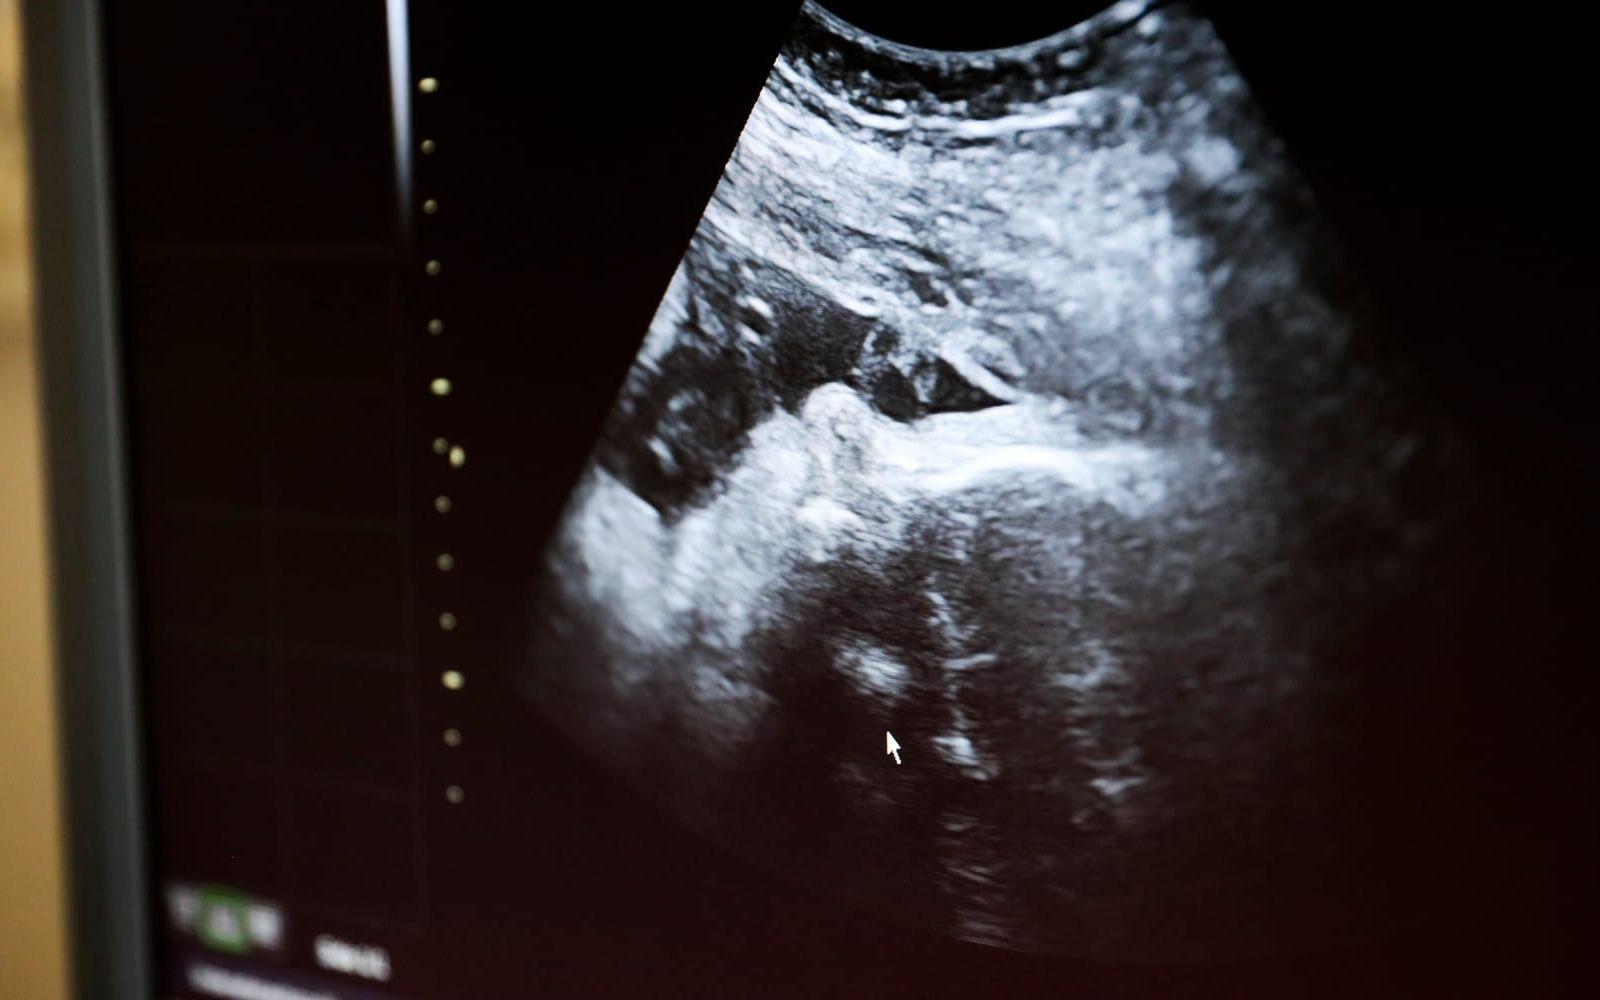

Enligt en SVT-undersökning planerar flera regioner att ersätta kub med det mer träffsäkra NIPT. Kub används i dag för att undersöka sannolikheten för kromosomavvikelser hos fostret. När kub visat på en avvikelse används ofta NIPT som uppföljning.

De nya EU-reglerna om medicinska tester införs senast 2028. De väntas leda till en generell utfasning av kub.

Det finns både för- och nackdelar med båda testerna. NIPT är mer träffsäkert, men medför högre kostnader. Samtidigt kan kub upptäcka avvikelser som NIPT inte kan.